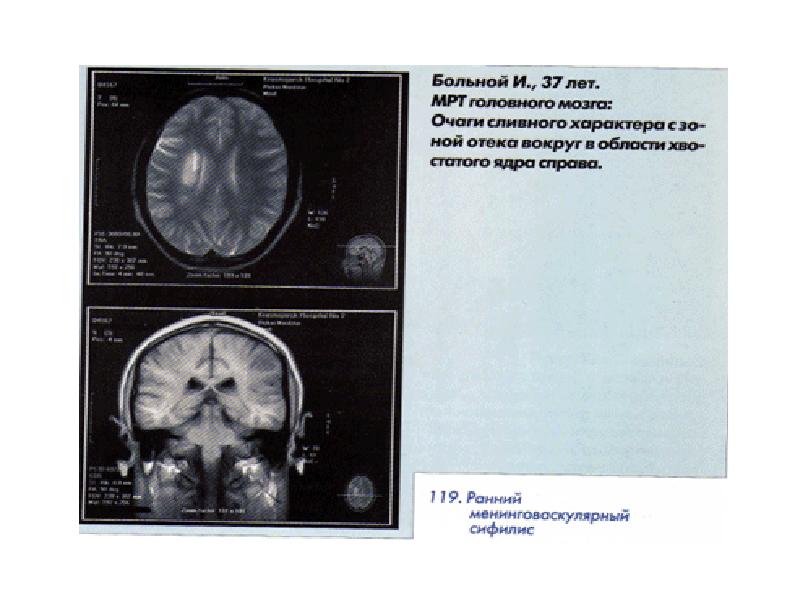

- 12. Ранний нейросифилис Клинические формы ОЧЕНЬ разнообразны! МЕНИНГИТЫ Серозные Базальной локализации Доброкачественные

- 13. Ранний нейросифилис 1.скрытый(асимптомный):легкая ГБ,ГК,тошното,КБ,ЧМН---повышение белка в ликворе 2. Острый сифилитический